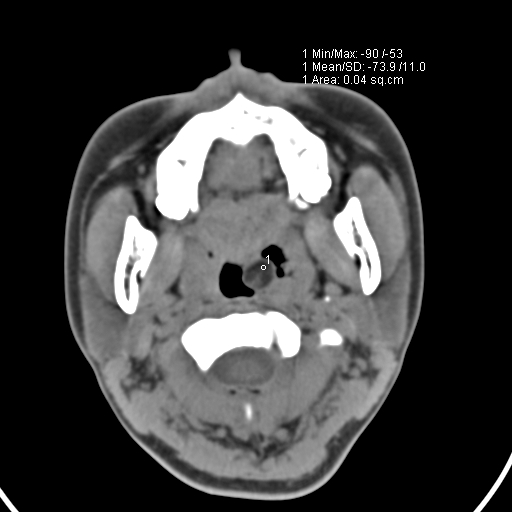

以下是引用zjzjr在2008-12-5 11:46:00的发言:[br]脂肪密度,壁有钙化.考虑口咽部皮样囊肿可能性大.双侧上颌窦炎,双侧下鼻甲粘膜肥厚.增殖腺肥大,扁桃体亦增大,考虑炎性.

以下是引用随光逐影在2008-12-5 18:27:00的发言:[br]1)考虑左侧茎突过长综合征并茎突舌骨韧带囊肿形成突入咽部;左侧咽部慢性炎症。2)鼻咽腺样体肥大。3)双侧扁桃体肿大。4)双侧上颌窦炎。5)双侧下鼻甲粘膜肥厚。